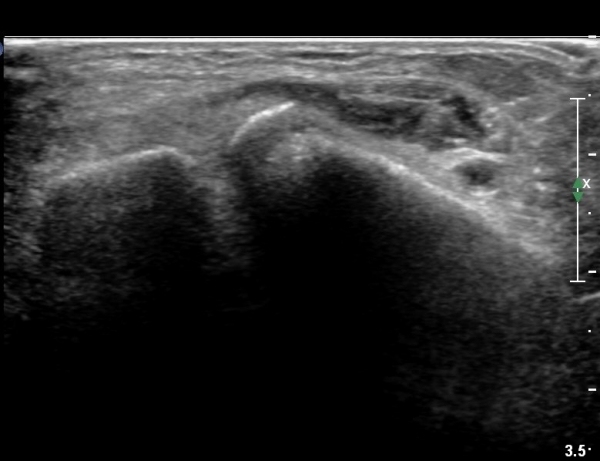

she revealed limping gait. on examination, there is swelling around ankle with limited ankle motion, localized tenderness at distal tibiofibular ligament and ATF ligament.

ÃÊÀ½ÆÄ °Ë»ç